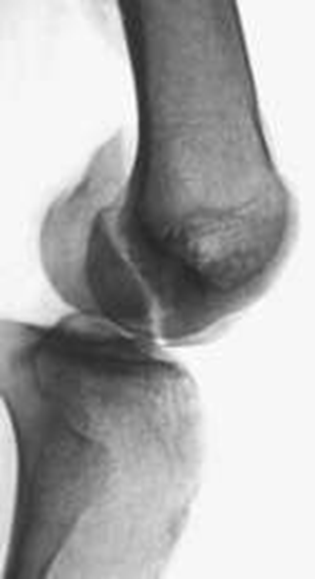

(4)Hoffa 骨折

股骨髁冠状面的骨折称为Hoffa 骨折,Friedrich Busch 在 1869 年首次描述此种类型的骨折,直到 1904 年 Hoffa 详细描述股骨髁外侧髁骨折并命名,随着时间发展,临床上逐渐把股骨内外髁冠状面的骨折都归于 Hoffa 骨折。

Hoffa 骨折属于关节内骨折,常伴髌骨、半月板、交叉韧带、副韧带及胫骨平台的损伤,由于其特殊的解剖结构,此型骨折的发生率极低, 在股骨远端骨折中不足 1%,一般发生在外侧髁。